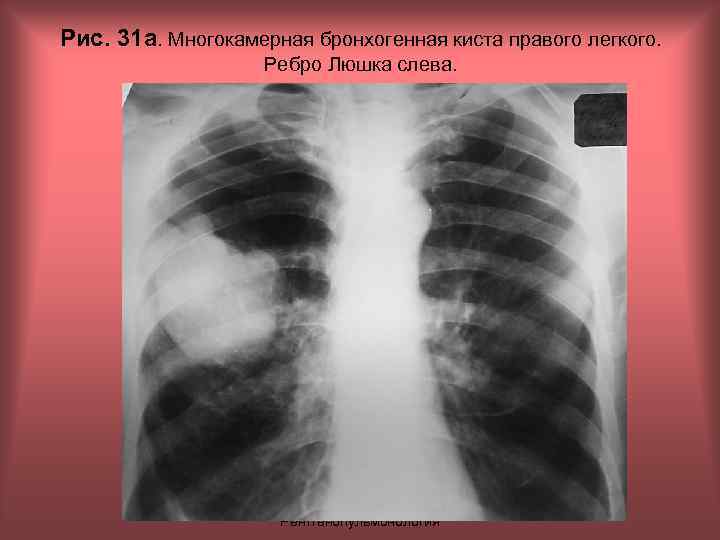

Рис. 31 а. Многокамерная бронхогенная киста правого легкого. Ребро Люшка слева. Н. С. Воротынцева, С. С. Гольев Рентгенопульмонология